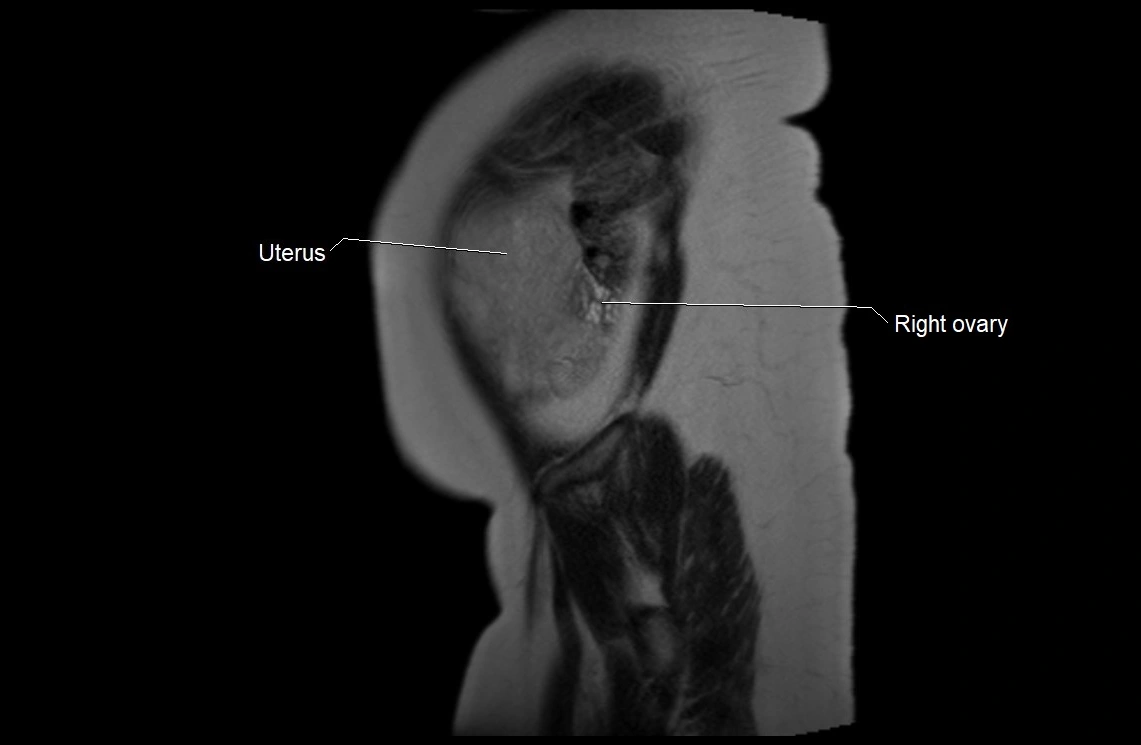

MRI Appearance

T2 HASTE (T2 GRE):

• Amniotic fluid shows very bright hyperintense signal

• Provides natural contrast against fetus and placenta

• Small particles (vernix) may appear as scattered hypointense foci within bright fluid

T1 GRE:

• Amniotic fluid shows low signal intensity (dark)

• Hemorrhage, infection, or proteinaceous content may cause focal or diffuse high signal intensity

MRI image

image